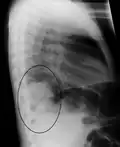

Right lower lobe pneumonia as seen on a lateral CXR

The discovery of x-rays made it possible to determine the anatomic type of pneumonia without direct examination of the lungs at autopsy and led to the development of a radiological classification. Early investigators distinguished between typical lobar pneumonia and atypical (e.g. Chlamydophila) or viral pneumonia using the location, distribution, and appearance of the opacities they saw on chest x-rays. Certain x-ray findings can be used to help predict the course of illness, although it is not possible to clearly determine the microbiologic cause of a pneumonia with x-rays alone.